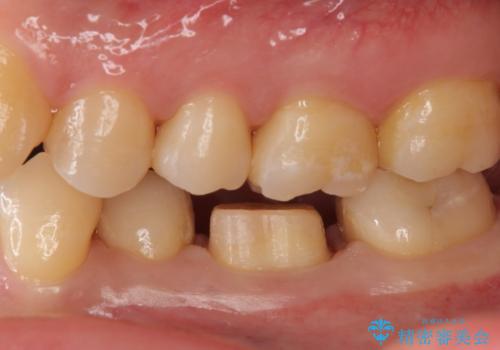

- 左下に詰めた樹脂の変色を主訴に来院されました。

同じ樹脂の材料で詰め直しをしたところでまた変色してしまうリスクが高いため、セラミックでの治療となりました。

樹脂の材料はどうしても変色などの劣化スピードが速いです。

樹脂の変色が気になる場合は、劣化しにくいセラミックに材料ごと変えることをお勧めします。